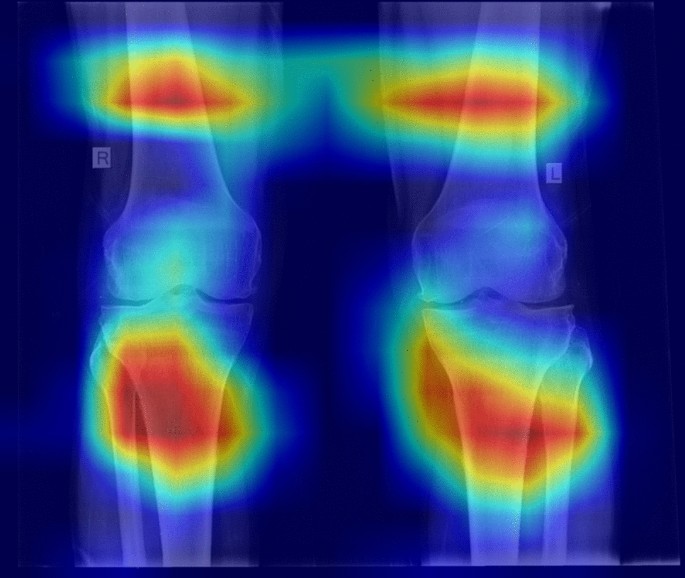

We also went through the examination of the power of these two types of models, via another method. We utilised heatmap visualisations to evaluate their effectiveness in detecting illness locations in medical pictures. The main goal was to assess the precision and comprehensibility with which each model identifies problematic regions. The heatmaps obtained showed that the ViT s16 model outperformed the VGG16 model in reliably identifying the affected areas. The heatmaps generated by the ViT s16 model offer a higher level of accuracy and clarity in identifying specific regions of pathology. This highlights its potential as a more efficient tool for detecting diseases in medical imaging applications. The results indicate that the sophisticated structure of the ViT s16, which utilises self-attention processes, provides notable benefits in medical picture analysis compared to the conventional convolutional method of VGG16. Figures 12 and 13 manifest the result of the comparison for aforementioned two models.